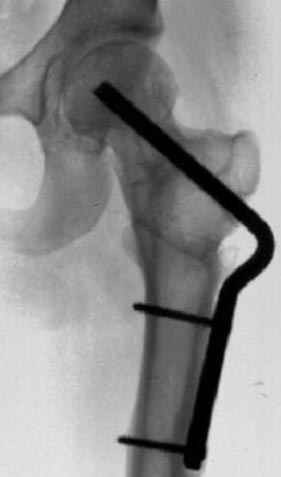

Несколько снимков из моей коллекции, чтобы разьяснить, почему мы до сих пор делаем различные варианты остеотомии.

На рисунке N1 предоперационный план лечения ложного сустава шейки бедра- линия ложного сустава, угол и направление введения импланта, клиновидная остеотомия в градусах и миллиметрах, второй снимок после коррекции, расчет, на сколько удлиняется конечность и размеры импланта;

N3 рисунок окончательный снимок, после операции моя рентгенограмма должен выглядеть примерно как эта картина. На N4 снимке клин перед удалением; N5 послеоперации 3 нед.; N6 окончательная рентгенограмма.